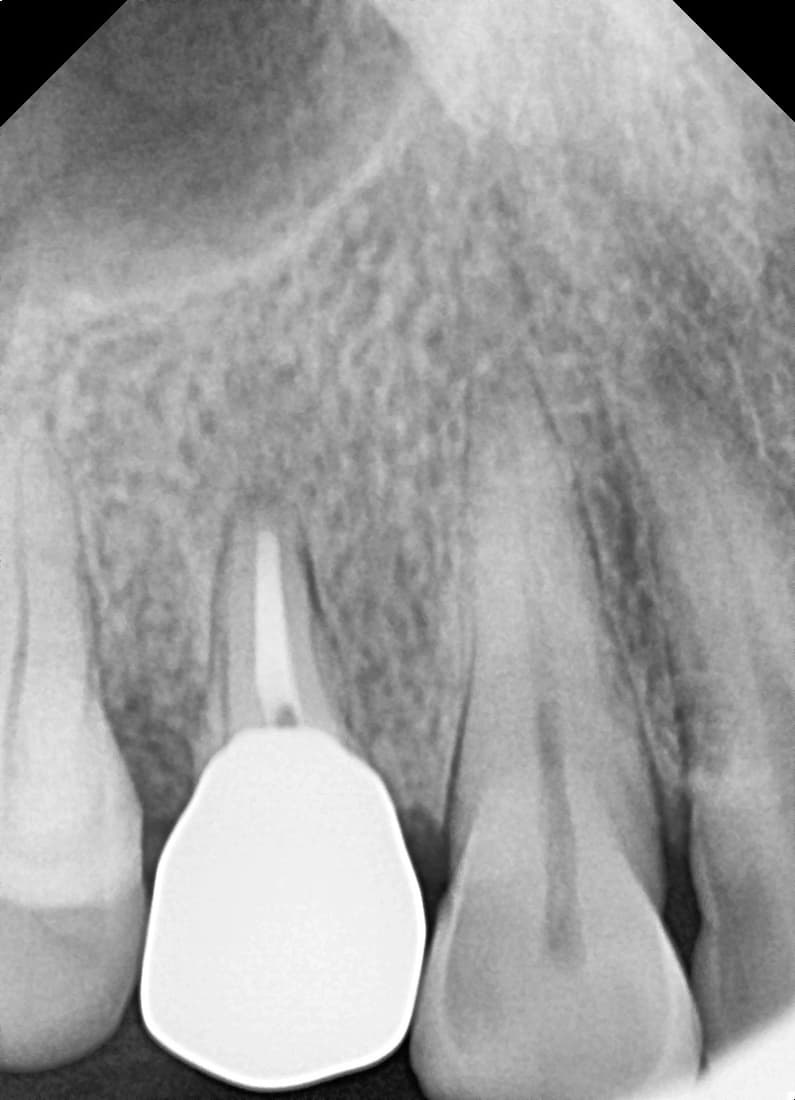

Apicoectomy

Front tooth with inflammation spreading to root tip

Before

After

Complete healing of lesion after root canal re-treatment and apicoectomy